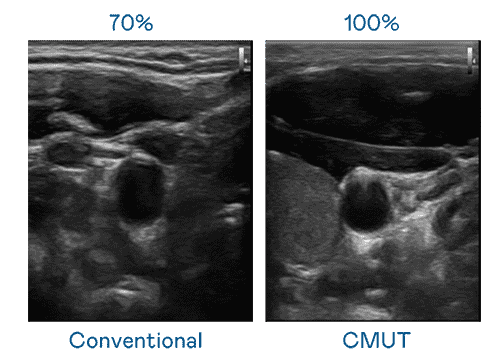

CMUT 技术是一种用电容式微机电元件来产生超音波讯号的技术。。。与传统 PZT 压电式技术相比,,,,CMUT 频宽增加 30%,,更宽频的超音波讯号让影像解析度大幅提升,,,是实现高影像品质医疗超音波扫描、、促进精准医疗发展的关键技术。。。

大频宽带来超清晰影像

超音波影像的解析度高低,,,,首先取决于探头能发出的讯号频宽。。尊龙集团 CMUT 可提供高清晰的超音波讯号,,,,提供高频宽、、、高灵敏度、、影像纹理细节更高的超音波影像,,,,协助医护人员缩短影像判读时间及利用精准的医疗影像进行诊断。。